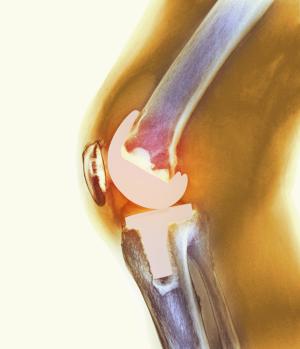

| тотальная | Полное удаление суставного сочленения, установка имплантата, идентичного по конструкции естественному аналогу |

Импланты коленного сустава

Протез не изготавливается для каждого человека индивидуально, но в каждом из них учтены особенности анатомии, возраста, пола. Медики учитывают даже дальнейший образ жизни и вес. Такой подход позволяет избежать трудностей при установке. Далее хирург-ортопед проводит проверку кинематики искусственного сустава в положении согнуть/разогнуть. Обнаруженные недочеты сразу исправляются.